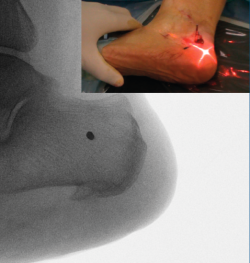

Figura 4. Imagen fluoroscópica de la fresa suelta introducida y su correspondencia en cirugía.

Ayudándose del mosquito para separar las partes blandas, se introduce una fresa Shannon 2 o 3 × 20 mm (FH Orthopedics, Mulhouse, Francia) en el vértice de la V. Comprobada la correcta posición de la fresa en la fluoroscopia (desconectando el motor de la fresa) (Figura 4), esta se avanza perpendicularmente al eje del calcáneo hasta atravesar la segunda cortical. Inclinando la fresa se pueden obtener diferentes desplazamientos, si bien, para conseguir un mayor desplazamiento, se recomienda avanzar perpendicularmente al eje. Si se quiere conseguir cierto efecto de descenso además de medialización de la tuberosidad se dirigiría la fresa en dirección de dorsolateral a plantomedial unos 15-30° respecto a la perpendicular del eje del calcáneo. Si lo que se quiere es obtener un efecto de elevación (beneficioso en el cavo posterior), la dirección sería la contraria, es decir, de lateroplantar a dorsomedial. Se podría obtener también acortamiento del calcáneo si la fresa se dirige de lateral distal a medial proximal, e incluso un alargamiento (de lateral proximal a medial distal), aunque esto último dificultaría el desplazamiento por la tensión de los tejidos(13).

Figura 5. Imagen fluoroscópica del trazo dorsal de la osteotomía y su correspondencia en cirugía.

La fresa se coloca en línea con el trazo de osteotomía dibujado en la piel, primero el dorsal y después el plantar (Figuras 5 y 6), y va cortando la pared lateral y el hueso esponjoso del calcáneo y progresando paulatinamente hasta alcanzar la segunda cortical y cortarla cuidadosamente. Se recomienda no superar en 6.000 rpm la velocidad de la fresa para evitar la osteonecrosis térmica. A pesar de que el procedimiento se realiza sin isquemia para que la sangre refrigere el calor de la fresa, se recomienda que el ayudante aporte suero salino para contribuir a tal efecto.